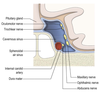

Entry of the ICA to the skull

Arises form the CCA and enters the middle fossa of the cranial cavity via the carotid canal.

Its course then follows a series of bends known as the carotid syphon, after which it passes through the cavernous sinus and then upwards on the medial aspect of the clinoid process, reaching the surface of the brain lateral to the optic chiasm.

What are the preterminal branches of the ICA?

Hypohpyseal

Opthalmic

Anterior choroidal

PComm

Hypophyseal arteries

Arise from the intra-cavernous section of the ICA to supply the neurohypophysis.

Also form the pituitary portal system.

Opthalmic artery

Passes into the orbit through the optic foramen.

Supplies the structures of the orbit, frontal and ethmoidal sinus, frontal part of scalp and dosrum of nose